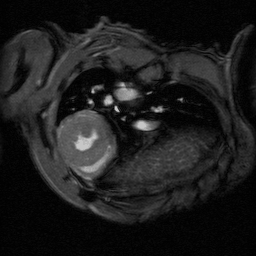

The ultra-high field of the BioSpec 152/11 provides extreme sensitivity for greatest resolution. Its streamlined design for mice studies makes handling simple, while its powerful software guarantees best results. It can be equipped with the MRI CryoProbe to increase sensitivity even further and together with the gradient strength of up to 1000 mT/m, highest resolution is achieved. It is built with nitrogen-free Ultra Shielded and helium Refrigerated (US/R) magnet technology for long service intervals

• MRI CryoProbe for exceptional increase in sensitivity